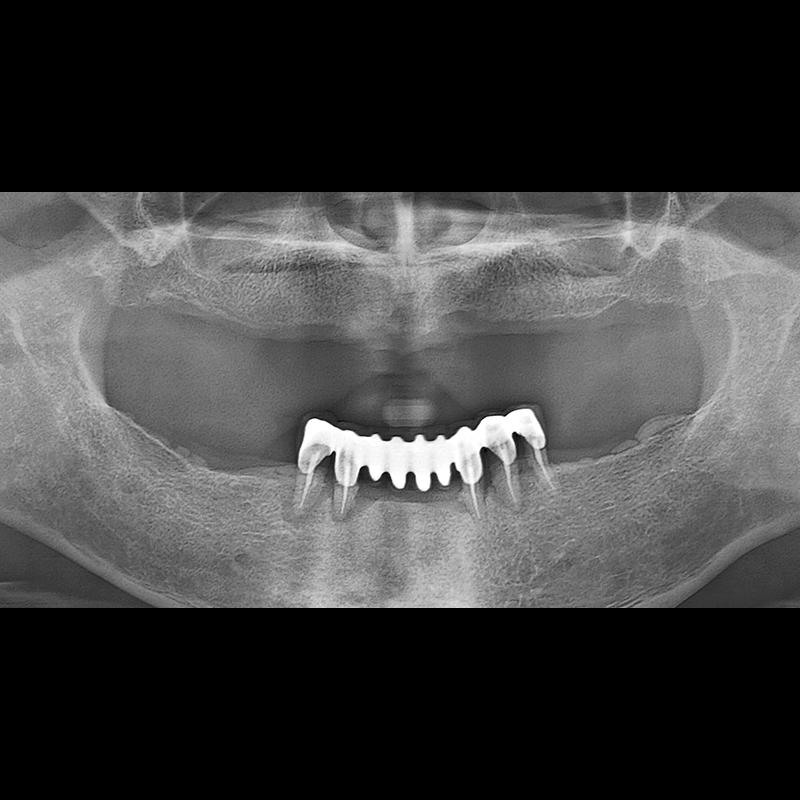

BEFORE AFTER

Implant before and after 2025.05.30

Implants were placed in the missing tooth and in the tooth position where it was difficult to save.